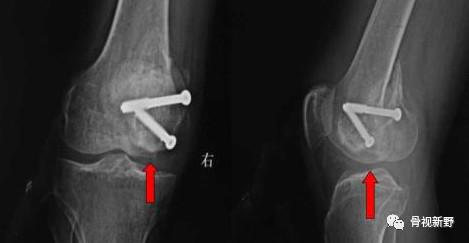

影像诊断:部分Hoffa骨折X线片不能提供明确的诊断,漏诊率较高。需要CT或MRI检查,并根据患者的病史、查体及影像学检查予以确诊。

部分Hoffa骨折普通X光片易漏诊

CT扫描在矢状位、轴位容易发现骨折及骨折线的走形方向